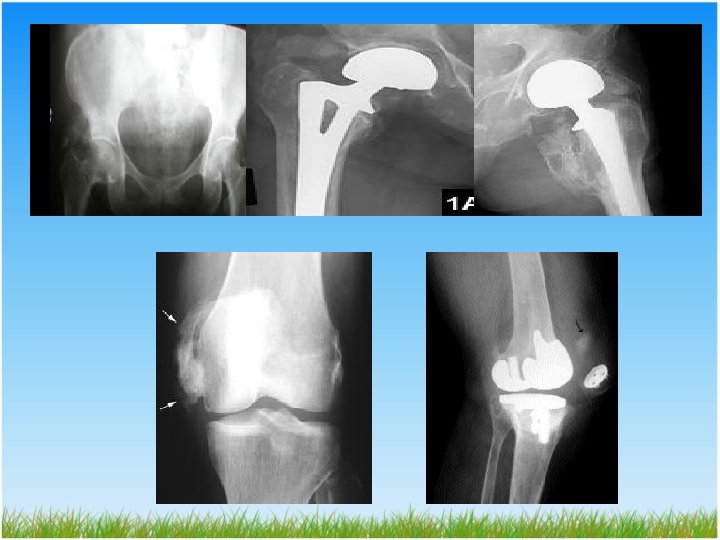

Total kalça artroplastisinde (TKA) HO • Görülme sıklığı %0. 6 -90 • Artroplastiden hemen sonra gelişmeye başlar. Birinci haftadan itibaren sintigrafik incelemede izlenebilir. • Ameliyat sonrası ilk üç ayda izlenmediyse daha sonra gelişme ihtimali oldukça düşüktür.

Brooker sınıflaması: Eklem aralığı azalması temel alınarak kemik miktarı 1 -4 arasında değerlendirilir. 1. derece Kalça çevresindeki yumuşak dokularda kemik adacıkları 2. derece Pelvis veya femur proksimal ucu arasında 1 cm den fazla mesafe 3. derece Kemik yüzleri arasında mesafe 1 cm den az 4. derece Kalçada belirgin kemik ankilozu

Total Diz Artroplastisinde HO • Sıklığı %0, 9 - 42 • Postoperatif 3 -8. haftalarda • Risk faktörleri: • • Operasyon sonrası diz fleksiyon kısıtlılığı Yüksek lomber kemik mineral yoğunluğu Operasyonda yoğun periost hasarı Erkek cinsiyet Romatoid artrit Anterior femoral kesi sırasında basamaklanma Kuadrisepsin zorlayıcı ekartasyonu ve midvastus girişimi

Derecelendirilme; (Figgie ve Goldberg) • Derece 0; HO bulgusu yok. • Derece 1; Spur oluşumu olmaksızın dizin en az bir kompartmanında ilerleyici HO • Derece 2; Spur formasyonuyla birlikte (>1 mm) dizin en az bir kompartmanında ilerleyici HO • Derece 3; Tam kemik ankilozu